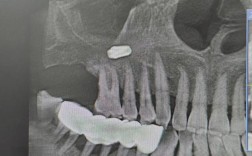

- 影像学检查: 拍摄口腔全景片(曲面断层片)和/或锥形束CT(CBCT),CBCT能非常精确地测量牙槽骨的高度、宽度、密度,观察神经管、上颌窦等重要解剖结构的位置,是评估种植可行性和制定手术方案的金标准。